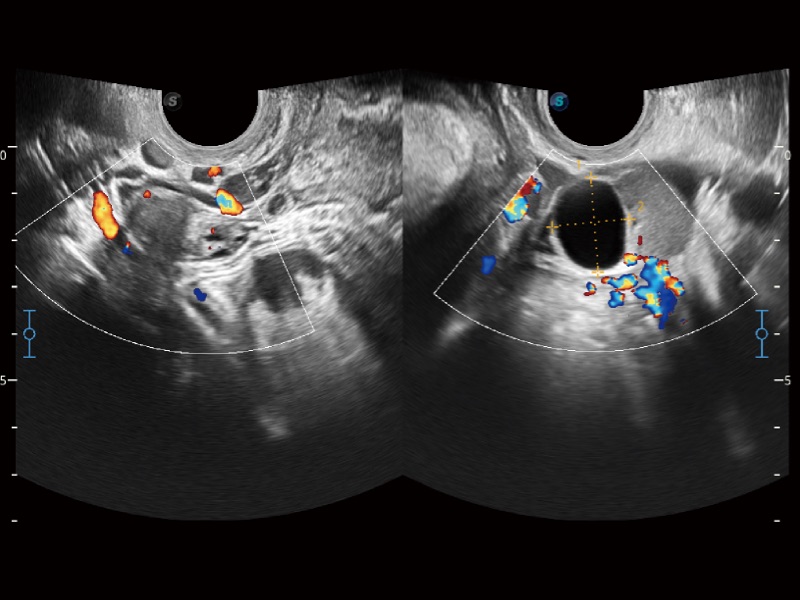

妇产科应用

微米成像技术大大提高了器官和病变的可见性。高清对比度分辨率将抑制斑点噪声,同时保持真实的组织结构。

高分辨率血流成像技术提高了对低速血流信号的检测能力。在提高空间分辨率的同时,也克服了血流外溢现象,为用户提供更加真实的血流动力学信息。